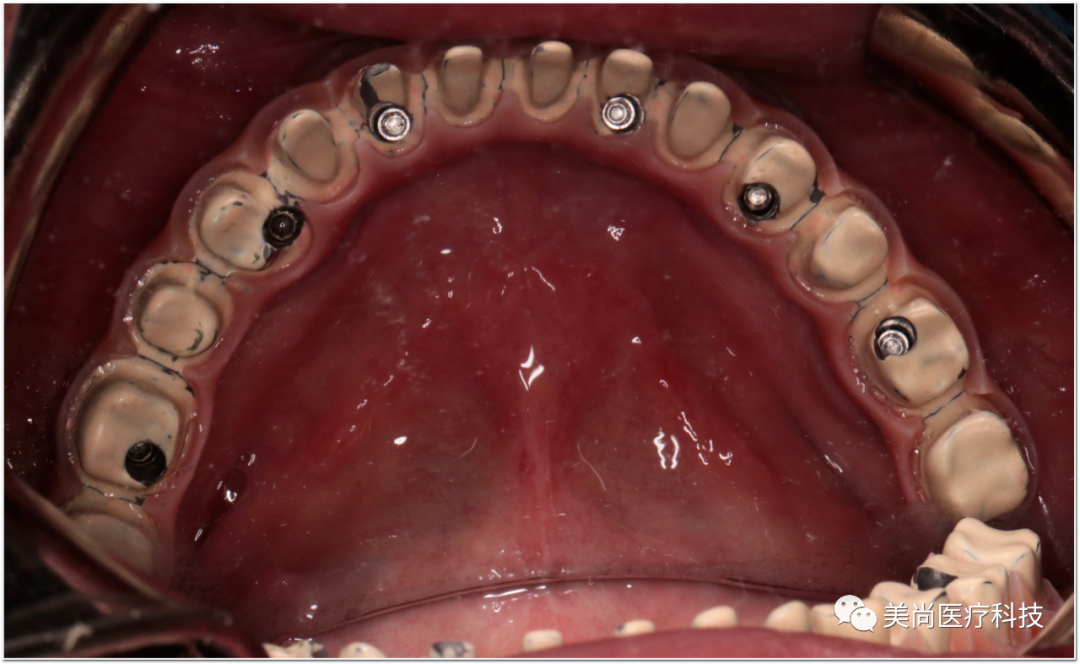

制作种植导板